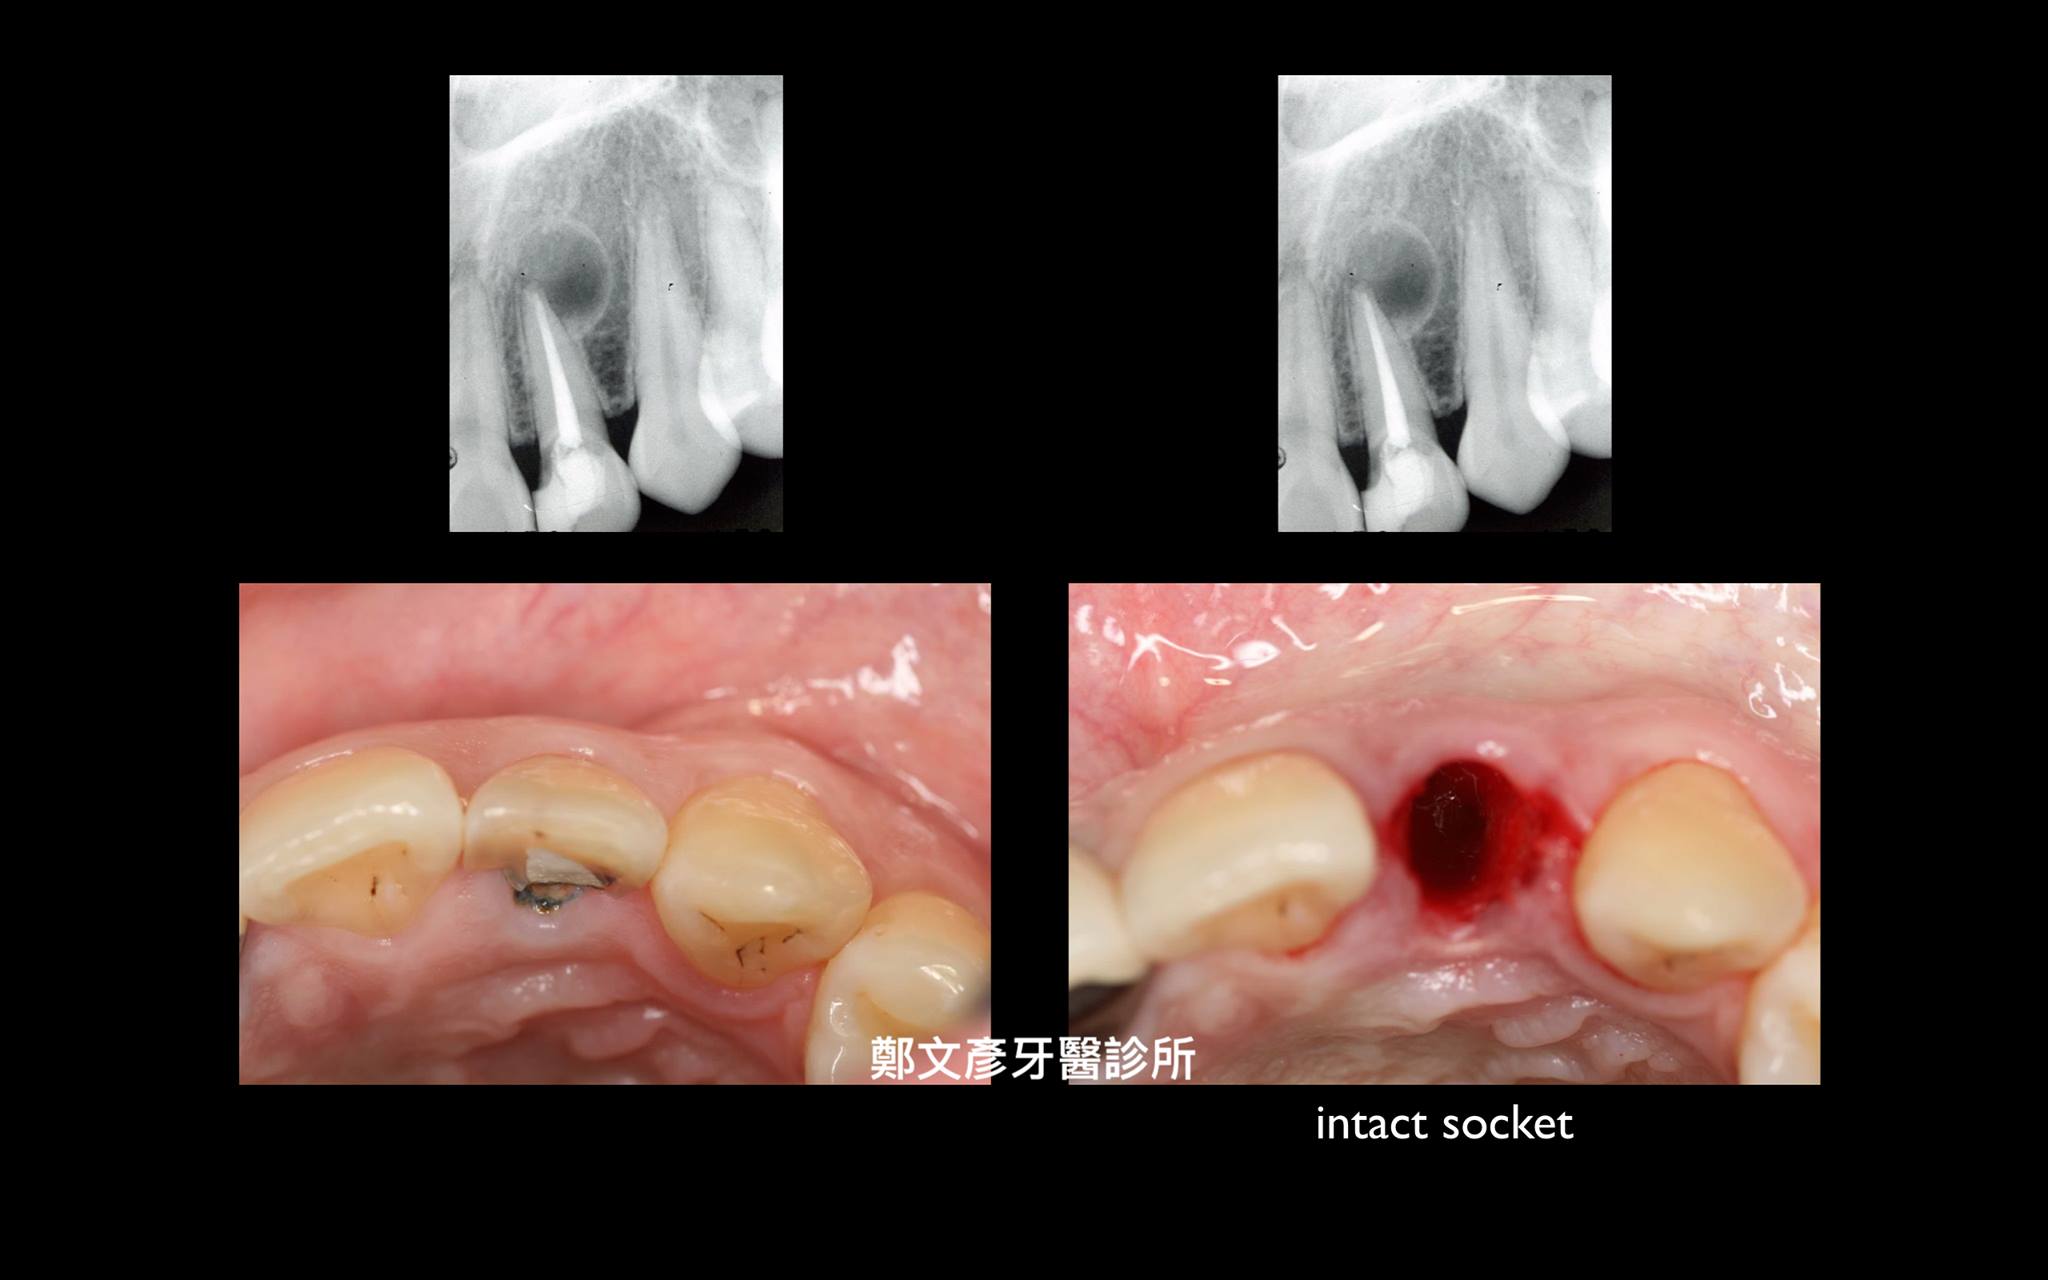

前牙植牙美學及軟組織轉移

植牙美學